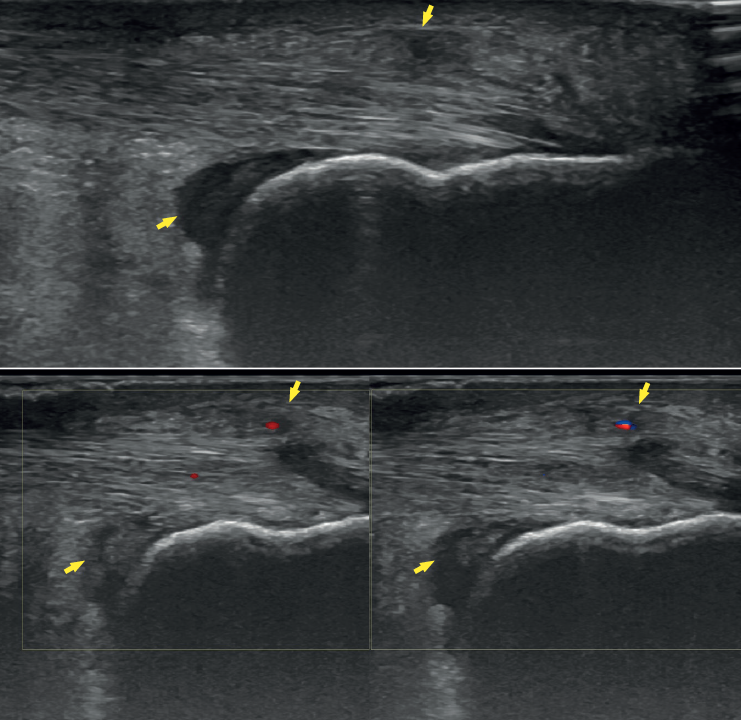

The dorsoplantar and sagittal views of both feet under loading conditions are indicated, together with the posteroanterior view of the ankles under loading conditions.

Figure 3. Plain radiography, Sagittal view with weight-bearing. Moderate calcifications in the insertion of the Achilles tendon with intratendinous enthesophyte. Morphological alterations of the posterior tuberosity of the calcaneus.

Plain radiography under loading conditions is the essential initial diagnostic tool(20). It allows us to assess alignments and dysmetria, to measure angles, to determine the morphology of the calcaneus and its posterior tuberosity, to characterise bone exostosis and increments in thickness of the retrocalcaneal soft tissues, and to plan surgical procedures (Figure 3).